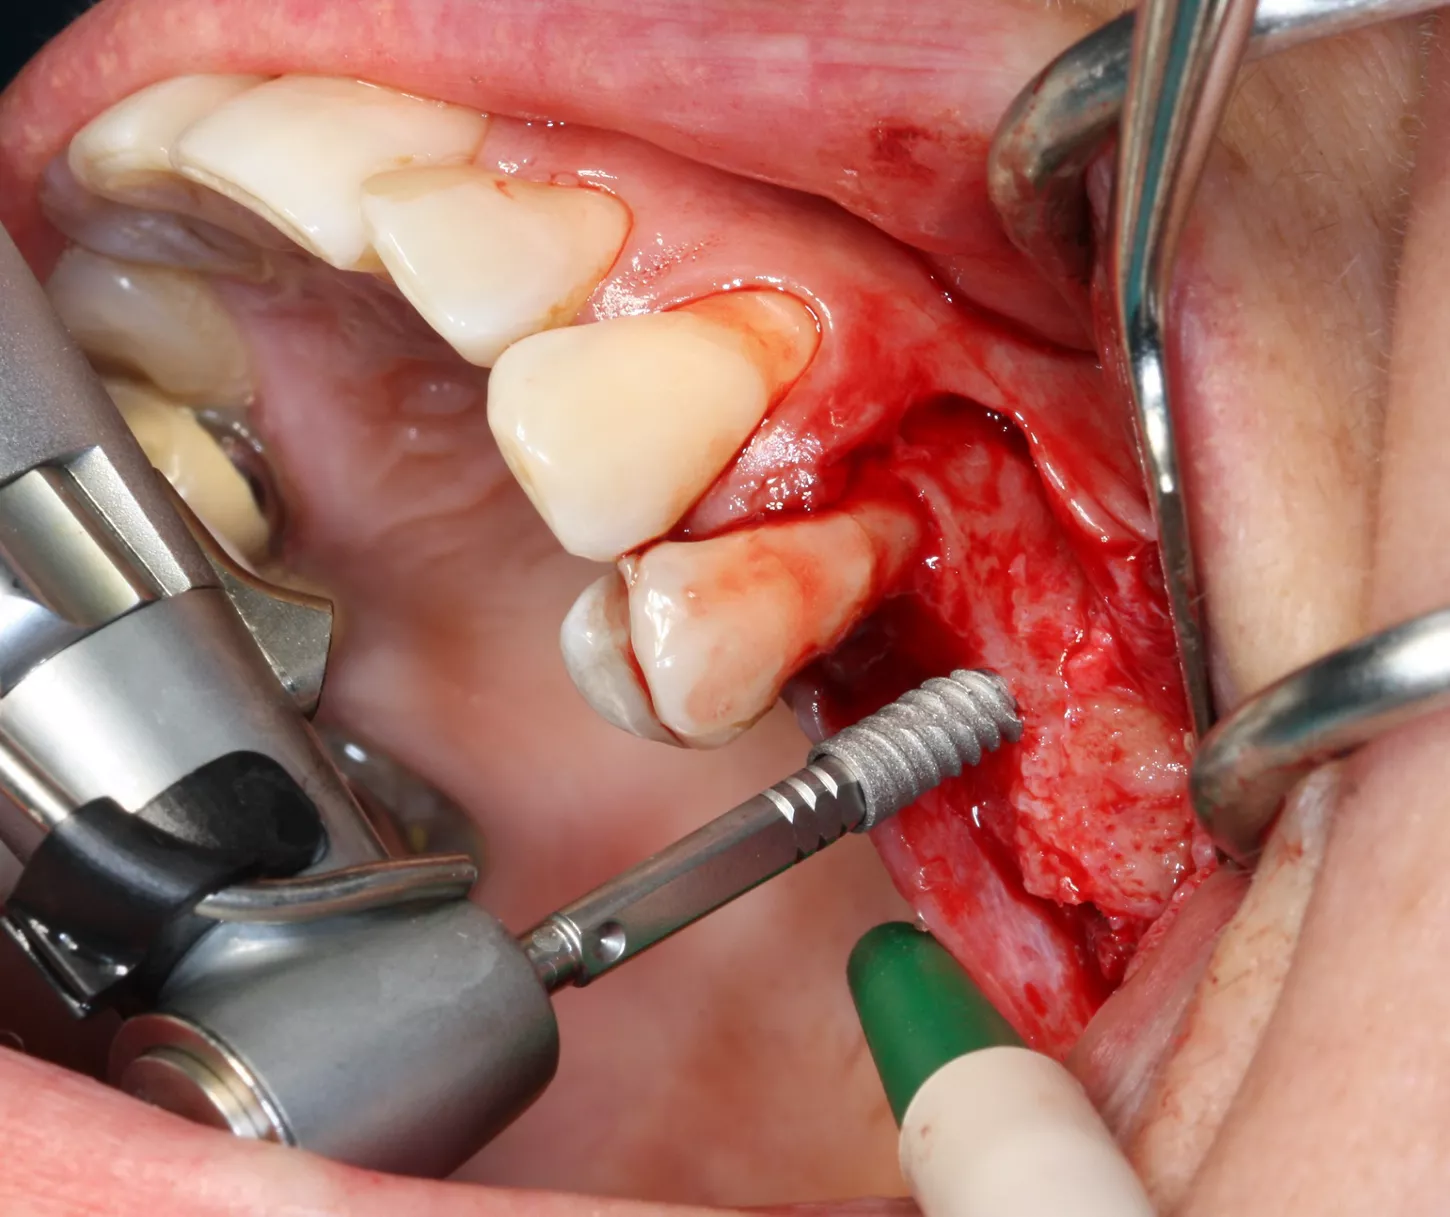

12a-b-c. The design of the Axiom X3® ensures atraumatic implant placement with the micro motor. The Axiom X3® also preserves bone, even if the ridge is thin and resorbed. Despite the meager quantity of vestibular cortical bone, there was no perforation or rupture of the crestal margin.

13. The implants were placed 0.5–1 mm subcrestally. Note the thinness of the vestibular cortical bone at the 25 implant on this occlusal view. Despite this, we achieved perfectly acceptable stability values of 19 and 20 Ncm.

14. Graft material added to the vestibular aspect of 25 to offset the bone loss and ensure long-term implant survival.